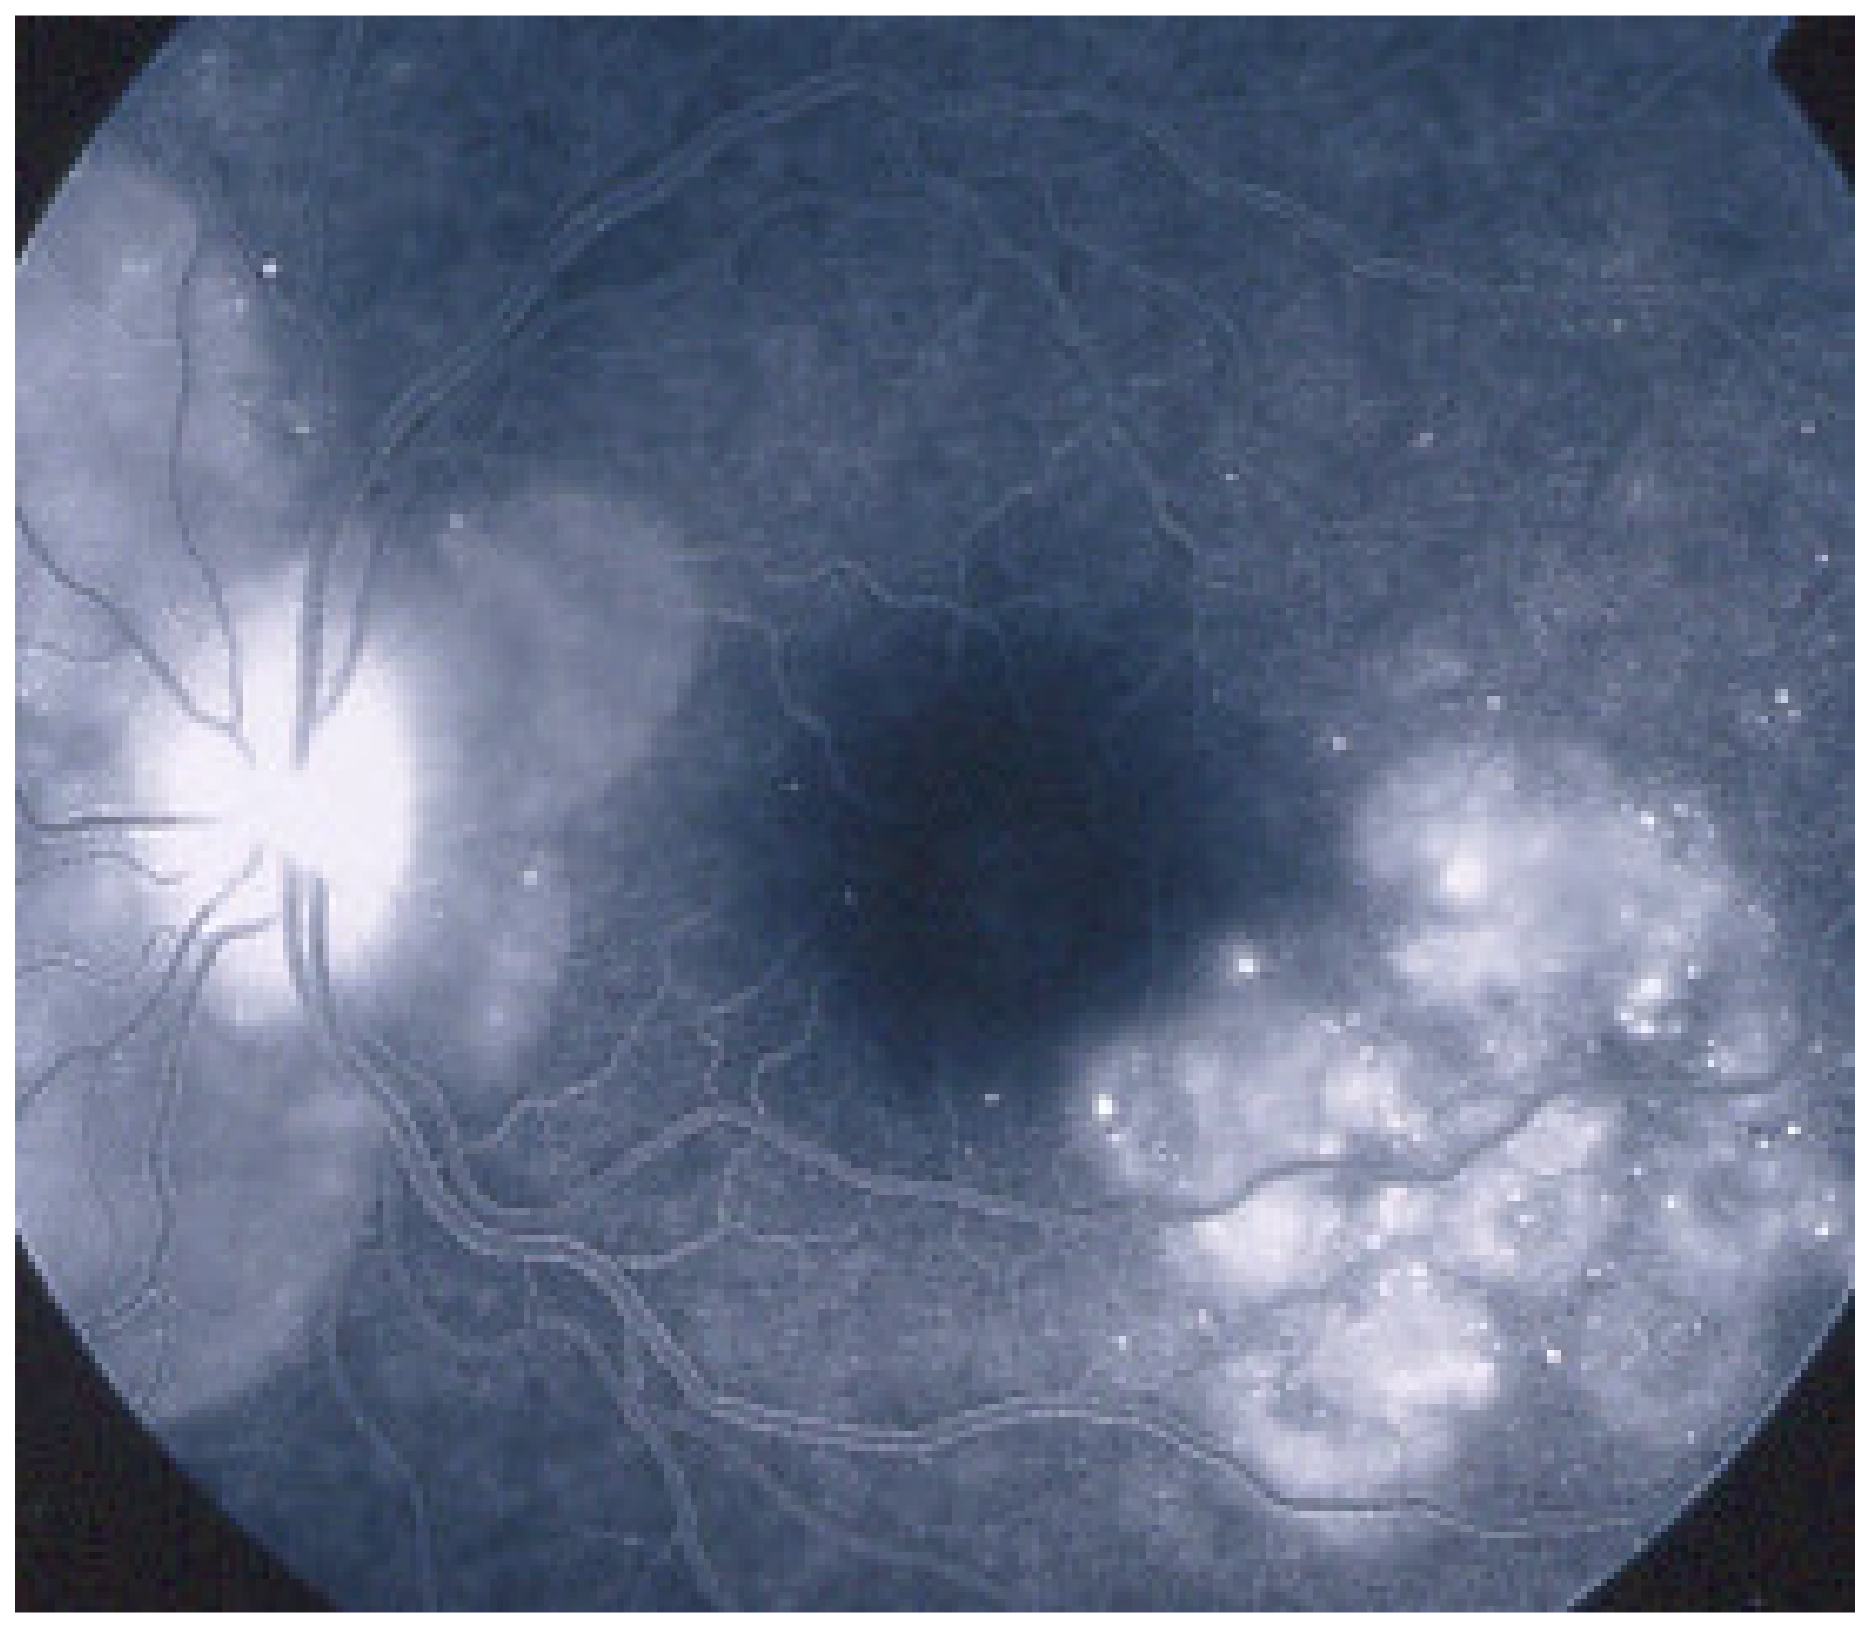

As the affected areas involved are significantly larger than in MEWDS, ICGA hypofluorescence is much more pronounced and widespread (Figure 10). The ischaemic consequences on the retina are also much more important than in MEWDS where ischaemia-induced FA hyperfluorescence remains usually faint. In contrast, in APMPPE/AMIC, FA shows early hypofluorescence due to choriocapillaris non-perfusion. In the later phase of FA, pronounced hyperfluorescence and even pooling occurs due to massively ischaemia-induced increased permeability of both the outer and inner retinal vascular plexuses, which correspond to the yellow discoloured plaques seen on fundus examination (Figure 9). Exudation and pooling in late FA frames can only come from retinal vessels in response to outer retinal ischaemia, as the underlying choroid is non-perfused (Figure 11 and Figure 12). FAF shows hyperautofluorescence in moderately involved areas (loss of photoreceptor outer segments) but hypoautofluorescence in areas with severe vascular drop out. SD-OCT shows loss of photoreceptor outer segments in moderately involved areas. OCTA shows vascular drop-out.

Figure 10.

APMPPE/AMIC. Geographic areas of ICGA hypofluorescence.